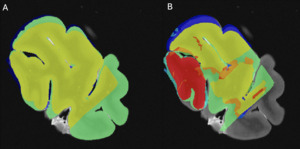

Tissue block-MRI-histology colocalization

Using Display software from the MINC toolkit, we segmented the surfaces of the same level of the MRI slide (Figure 3A) and the photograph of the tissue block (Figure 3B) registered to the corresponding histology section (Figure 3C). The histology sections were segmented by an expert with more than 8 years of experience (EMF), creating the following masks: Label 1 (Red)=Non-folded/Non-torn tissue (Good quality); Label 2 (Green)=Folded tissue; Label 3 (Blue)=Torn tissue; and Label 4 (Cyan)=Non-folded/Non-torn tissue that was not parallel to the MRI plane (Good quality but off plane) (Figure 3C). The surface of each mask was calculated as number of pixels in the MRI image space by transforming the histology and tissue block images to the MRI image space using the generation transforms. The MRI and photo block masks (Figure 3A-B) were then overlapped (Figure 4A) to assess the amount of tissue that was cut from the scanned block to be able to fit the vibratome. Then, the overlap of the histology mask (Label 1, Non-folded/Non-Teared tissue) and the photo block mask (Figure 3B-C and Figure 4B) was used to assess the percentage of tissue loss in the histology sections. Dice Kappas of the overlapped masks were also calculated to assess the amount of overlap. All measurements were generated automatically using an in-house MATLAB script. The percentage of tissue showing Good quality was then compared according to the fixatives and the staining types. We also assessed the mean percentage of Folded tissue and Torn tissue for each group to assess if the quality of the histology section affected the registration quality.

Figure 3.Masks created using Display to assess histology-MRI colocalization.

Masks were created for A) MRI slide registered to the histology section; B) Photo of the block cut to fit in the vibratome, registered to the MRI-histology section; C) Histology section photomicrographs. Red masks=Non-folded/Non-torn tissue (Good quality); Green masks=Folded tissue; Blue masks=Torn tissue; and Cyan blue= Non-folded/Non-torn tissue that was not parallel to the MRI plane (Good quality but off plane).

A close-up of a brain AI-generated content may be incorrect.

Figure 4.Overlap of the masks segmented to assess the amount of histology tissue colocalizing with MRI scans.

A) Overlap of the MRI plane and block photo masks that was considered as the target for assessment of the histology sections that co-localized. B) Overlap of the histology (with the four labels) to the block photo masks that is overlapped with the MRI picture, which was assessed according to the two groups (fixatives and type of staining).